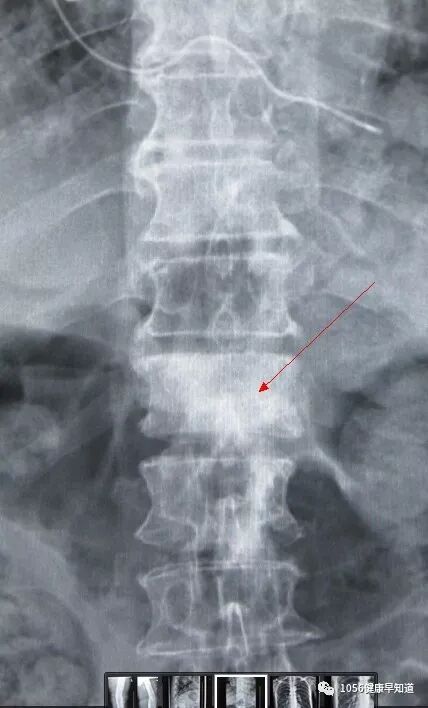

肿瘤患者在治疗原发肿瘤的同时,应该定期全身检查,以早期发现肿瘤转移。而对于骨转移,有以下几种检查可以帮助早期发现:同位素骨扫描是检查骨骼是否遭受癌细胞侵犯的高度敏感的方法之一,有研究表明它可以早于X线检查6个月发现骨转移灶。如果通过骨扫描筛查怀疑为骨转移,还可以进一步 做X线检查、CT、MRI或PET/CT检查确诊。X线检查经济实惠;CT准确性优于X线检查,对骨皮质病变精确性高;MRI(磁共振)检查可同时观察到脊髓、神经和软组织遭肿瘤侵害的情况,对指导治疗有重要作用;PET/CT检查,可以发现一般手段难以发现的微小病变。如上述检查都不能明确,还有骨穿刺活检的办法,可以明确骨转移瘤的病理类型。

在骨转移瘤中,脊柱转移瘤是最为常见的一种,它的相关症状包括:胸背痛、脊髓受压神经功能障碍、双下肢无力、行走障碍等。手术是解决这部分病人疼痛、恢复正常功能最直接有效的治疗方法。对于经评估能耐受手术的患者进行手术,尤其是早期完整切除肿瘤(En bloc手术)可以达到较满意的效果,包括稳定脊柱,解除肿瘤或骨折块对脊髓的压迫,缓解疼痛。对于脊柱肿瘤引起截瘫的患者,更应考虑尽快手术治疗,若拖延手术时间,会造成脊髓损伤向不可逆发展,丧失最佳治疗时机。外科手术治疗脊柱转移瘤的目标是:①恢复或保留充分的神经功能;②缓解疼痛;③切除肿瘤或肿瘤减压;④确保即时或永久的脊柱稳定。手术适应证:对预期生存期>6个月的脊柱转移瘤患者,符合以下条件之一时,则应该考虑外科手术治疗:①脊柱不稳与畸形,椎体病理性骨折压迫脊髓、马尾和(或)神经根引起进行性神经功能损害者;②顽固性疼痛,经非手术治疗无效者;③转移灶对放化疗不敏感或经放化疗后复发引起脊髓压迫者;④未知原发肿瘤类型,需明确病理诊断者。